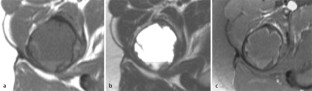

MRI morphology of bone tumors and tumor-like lesions

Für das Staging und die Charakterisierung von Knochentumoren und tumorähnlichen Läsionen ist in der Magnetresonanztomographie (MRT) der Einsatz von Spinechosequenzen erforderlich. Die MRT hat nur einen geringen Stellenwert in der Bestimmung der Dignität. Obwohl viele Knochentumoren und tumorähnliche Läsionen eine vergleichbare Morphologie in dieser bildgebenden Modalität aufweisen, können einige Tumorentitäten mittels MRT recht zuverlässig diagnostiziert werden. Hierzu zählen Knorpeltumoren, die solitäre und aneurysmatische Knochenzyste, der Riesenzelltumor, fetthaltige Läsionen und bis zu einem gewissen Grad auch das Osteoidosteom und das Osteoblastom. Es werden praktische Tipps gegeben, wann bei Tumorverdacht die MRT eingesetzt werden sollte, wie bei einem zufällig bei einer MRT gefundenen Tumor die Untersuchung modifiziert werden sollte und welcher Tumor vorliegen könnte.

Spin-echo sequences are mandatory at MRI for staging and characterization of bone tumors and tumor-like lesions. MRI is of minor value in the estimation of the malignant potential of an osseous lesion. Although many bone tumors and tumor-like lesions present similar morphology at MRI, some entities can be diagnosed with good reliability. These include chondrogenic tumors, solitary and aneurysmal bone cysts, giant cell tumors, lesions containing fatty tissue and, to a certain extent, osteoid-osteomas and osteoblastomas. Practical advice is given regarding when to perform a MRI study in cases of tumor suspicion. Further advices are given for cases a tumor is found incidentally at a MRI study, how to modify the study and which kind of tumor may be present.